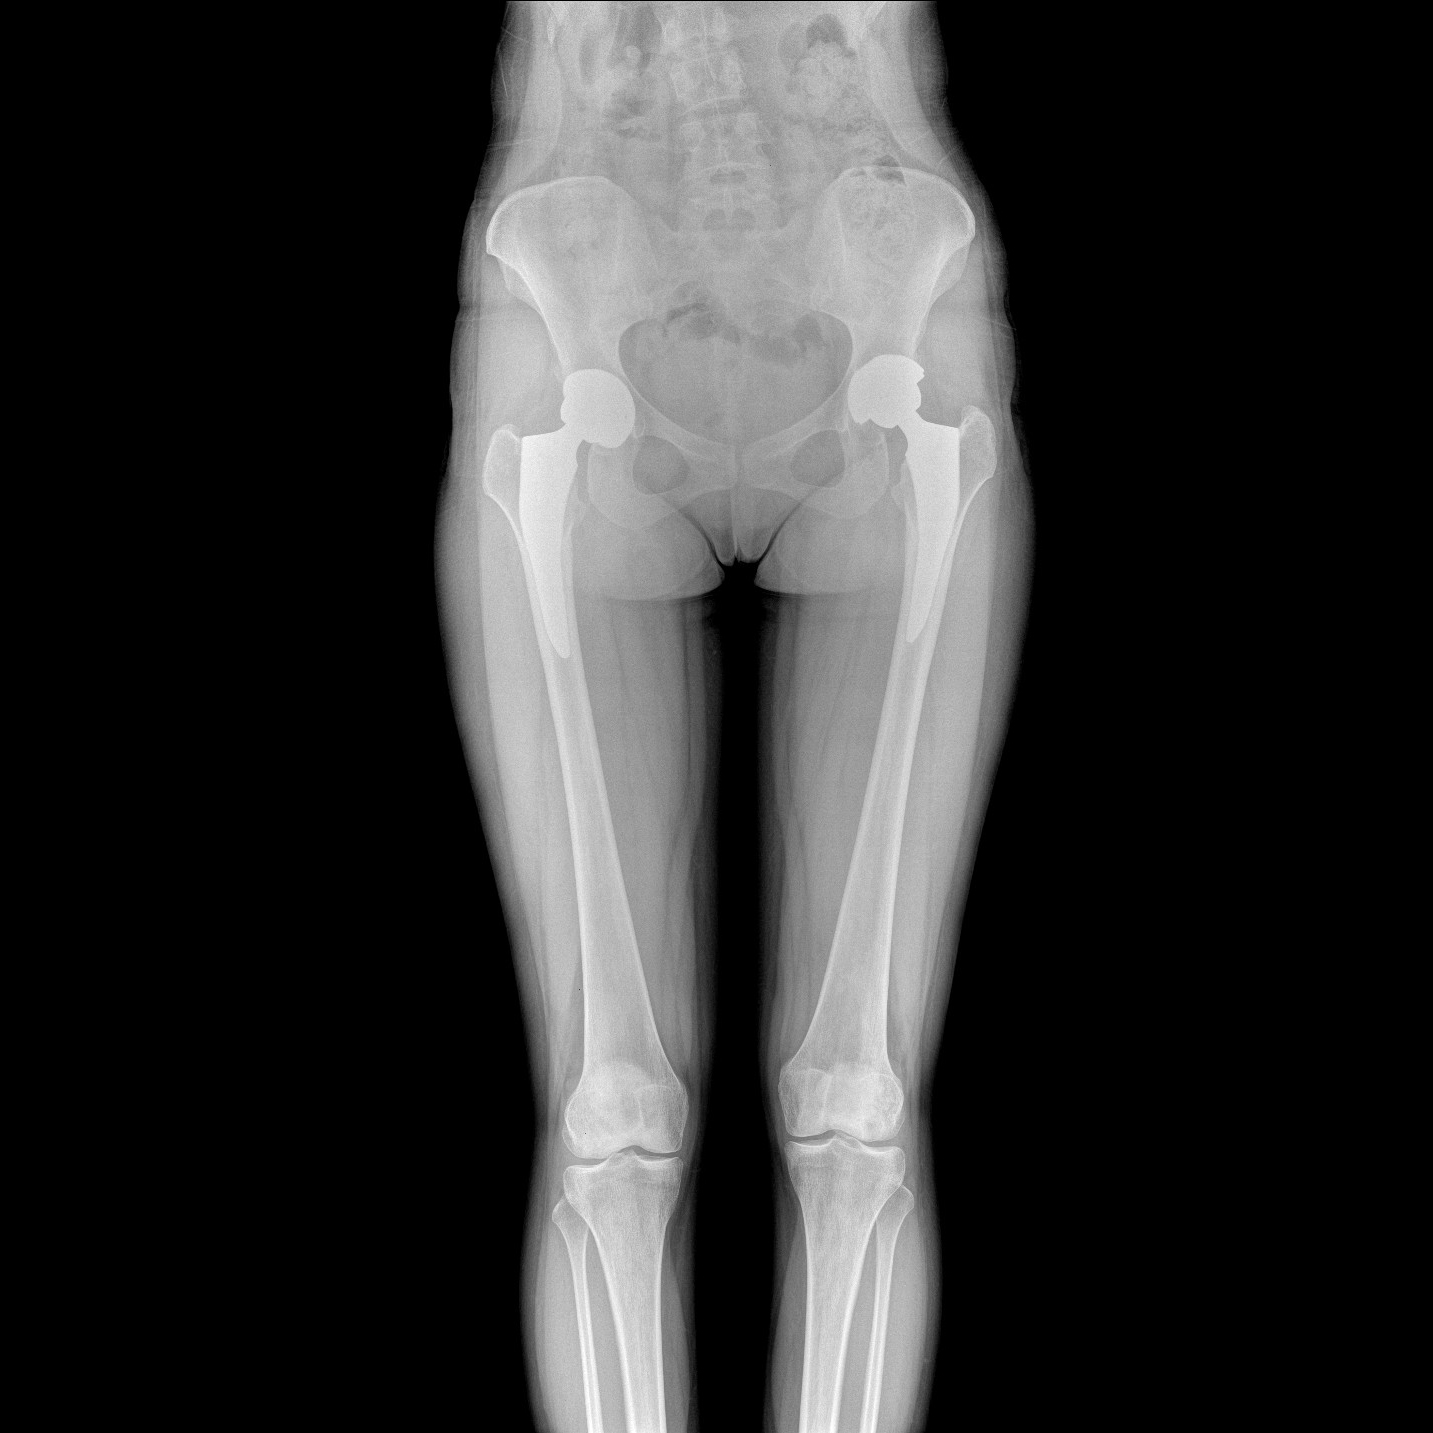

支持全脊柱攝影、雙下肢攝影、脊髓造影、復雜創(chuàng)傷、人工關節(jié)置換、關節(jié)損傷的修復重建等大視野臨床應用

17"*34"有效視野,一次成像不拼接。相較于多張攝影再軟件拼接的DR設備,PLX8600解決了拼接圖像存在密度不均勻,拼接處圖像配準和放大效應等問題,給臨床帶來了大視野影像解決方案,可一次性覆蓋全脊柱或雙下肢影像。

除常規(guī)靜態(tài)攝影外,PLX8600大平板具備動態(tài)透視和點片功能,透視采集功能可支持大視野、多角度的可視化觀察。通過可視化的動態(tài)影像,配合點片功能,能夠很好的觀察復雜部位病灶,有效的抓取關鍵幀,降低患者多次攝片的概率。如:全脊柱狀態(tài)評估、長骨關節(jié)活動度、下肢靜脈造影瓣膜功能評估、消化道功能評估、脊髓造影等更多大視野臨床應用。